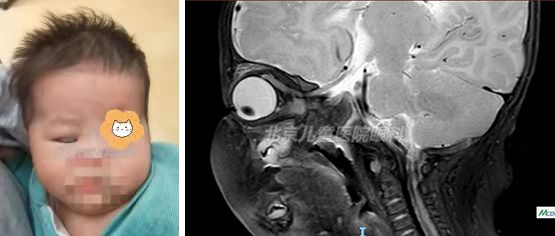

小亮生后3天不睁眼,开始睁眼时,家长发现看不到孩子右眼“黑眼球”,遍寻各大医院救治,院外曾诊断为 “先天性小眼球”、 “眼眶肿物”。但因患儿年龄小,病情复杂,被很多专业医生推荐到北京儿童医院救治。

眼科李宁东教授初次接诊时,小亮仅46天大,右眼角膜隐藏于下睑。经李宁东教授、刘雯医生详细检查,并经影像中心、眼科眼眶专业医生会诊,确诊为“先天性右眼眼外肌纤维化”。患儿右眼角膜(俗称黑眼球)隐藏于下眼睑,这样长期以来将使右眼无法接受视觉刺激,出现重度弱视,使患儿右眼丧失视功能。除此之外,该病还将严重影响小亮的外观,损害孩子的身心健康,因此需要尽快进行治疗。

经过充分的术前准备,在医务处、麻醉科等部门的大力支持下,李宁东教授于近日为刚满两个月的小亮实施了手术。手术中探查发现,小亮眼外肌严重发育不良,没有弹性,特别是右眼下直肌挛缩程度更加严重,将眼球固定于下转位,使眼球完全不能上转。而且患儿年龄小,眼眶区域解剖结构狭窄,几乎无法直视下看到要钩取的肌肉。最终李宁东教授凭借多年丰富的临床经验,几乎完全是靠手感从眶深部钩取到了挛缩的下直肌。在将下直肌离断的那一瞬间,小亮眼球的限制因素解除掉,被“藏起来”的黑眼球出现在大家面前时,手术室一片欢呼!

在北京儿童医院医护人员的精心照顾下,小亮在术后未出现任何全身不适症状,出院时右眼已处于正中位。小亮的视觉发育正处于关键时期,早期手术可以使他的右眼更早地接受外界视觉环境的刺激,为今后视力发育提供更好的保障。小亮妈妈在出院时特意跟李宁东教授说,真是没想到短时间内就为孩子进行了这么成功的手术,还是北京儿童医院实力强!